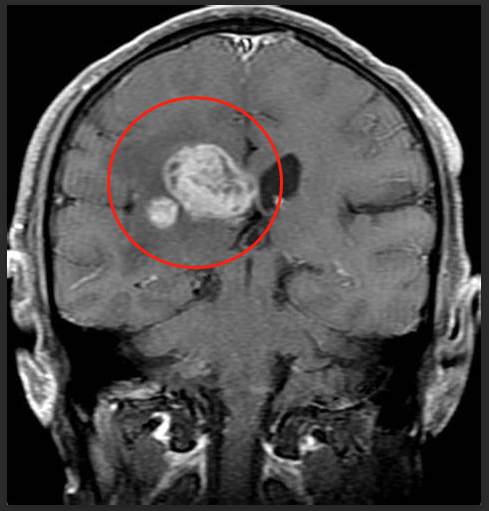

丘脑胶质瘤影像资料

影像学特征为丘脑胶质瘤的组织学和治疗方案提供了重要线索。前沿的神经影像学提供了更多关于这些病变的代谢和生理学信息,从而有助于诊断和随访。与临床表现相似,这些肿瘤的影像学特征因恶性程度不同而不同。高达20%的肿瘤是实性和囊性钙化。此外,虽然大多数恶性胶质瘤表现为瘤周水肿、强化和坏死,但一些高级别肿瘤可能没有这些特征,这可能会降低基于常规影像学的肿瘤分类和分级的可靠性。前沿的MRI技术,如灌注MRI和MRS,可以提供更多的信息来支持肿瘤的分类。在磁共振灌注成像上,与高级别肿瘤相比,低级别肿瘤的局部脑血容量相对较低。在MRS上,恶性肿瘤如胶质母细胞瘤表现出高胆碱峰,低N-乙酰天冬氨酸峰和高胆碱-肌酸比值。此外,与坏死相关的脂质和乳酸水平升高有助于将胶质母细胞瘤与高级胶质瘤(如间变性星形细胞瘤)区分开来。